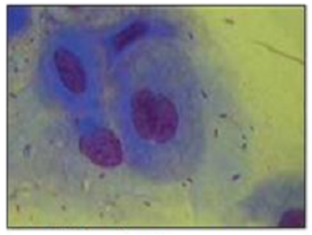

Перепечаев К.А., ветеринарный офтальмолог, микрохирург, к.б.н. Данная статья представляет из себя отдельные части оригинальной КНИГИ: ЭКСПРЕСС-ДИАГНОСТИКА ХРОНИЧЕСКИХ ВИРУСНЫХ ИНФЕКЦИЙ КОШЕК В ВЕТЕРИНАРНОЙ ОФТАЛЬМОЛОГИИ (коронавирус, вирус иммунодефицита и лейкоза). Авторы: Перепечаев К.А., Меньшенина Е.С., опубликована в 2020 году совместно с ООО «Ветэксперт» ЧАСТЬ 2. Вирус лейкоза кошек / Feline Leukaemia Virus- FeLV По нашим данным (за период 2012-2019 гг.) вирус лейкоза кошек встречается значительно реже, чем коронавирус...

Перепечаев К.А., ветеринарный офтальмолог, микрохирург, к.б.н. Данная статья представляет из себя отдельные части оригинальной КНИГИ: ЭКСПРЕСС-ДИАГНОСТИКА ХРОНИЧЕСКИХ ВИРУСНЫХ ИНФЕКЦИЙ КОШЕК В ВЕТЕРИНАРНОЙ ОФТАЛЬМОЛОГИИ (коронавирус, вирус иммунодефицита и лейкоза). Авторы: Перепечаев К.А., Меньшенина Е.С., опубликована в 2020 году совместно с ООО «Ветэксперт» (Рис 1). 1. ВВЕДЕНИЕ Хронические вирусные инфекции кошек (ХВИ – общий термин, объединяющий латентные вирусные инфекции кошек: лейкоз, иммунодефицит,...